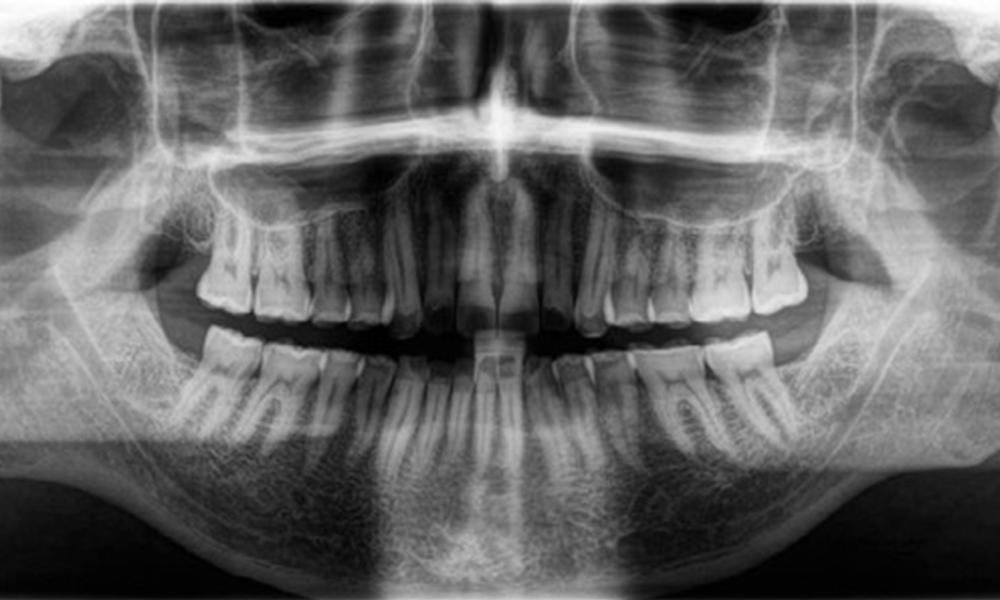

The patient has full dentition with a total of 28 teeth. There were noteworthy erosions and attritions. (Fig. 4, Fig. 5). Due to bruxism, the patient has been wearing a splint with an adjusted bite block at night for many years. The erosions were caused by long-term consumption of isotonic beverages. No periodontal bone loss or active caries were observed.

Full complement of adult teeth with no caries or radiologically recognizable bone loss was observed (Fig. 6). Radiological enamel and cusp loss were particularly evident on 36 and 37.